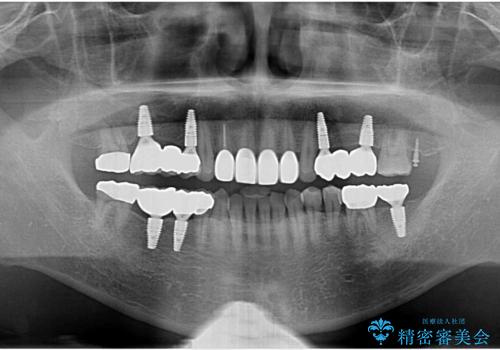

[ 前歯のねじれ・がたつき ] マウスピース矯正

- 前歯のねじれやがたつきを綺麗に並べたい、と矯正治療を希望され来院されました。

IPR(歯の間をすく)をくみこみ、がたつきを取り、かつ出っ歯にならないような矯正治療の計画をマウスピース矯正システムインビザラインで立てます。

気になっていたがたつき、ねじれが取れ、綺麗な歯並びに満足いただくことができました。